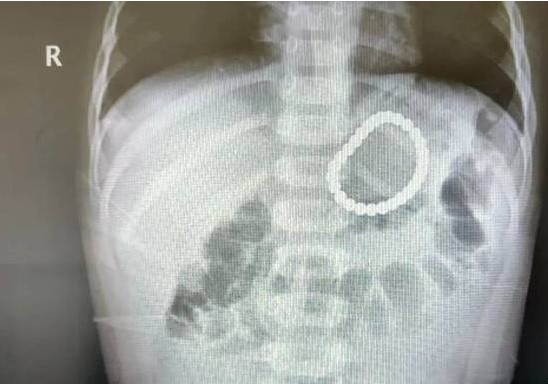

送医时,距幼童玩耍磁力珠已超过20个小时,医生赶紧联系放射科,果不其然,在X光下,幼童的左上腹部出现一个串珠样的异物。

幸运的是,这28颗磁力珠被幼童吞咽后没有分离,除了部分胃黏膜损伤外,没有出现其他被夹住、穿孔等情况。

幸运的是,这28颗磁力珠被幼童吞咽后没有分离,幼童除了部分胃黏膜损伤外,没有出现其他被夹住、穿孔等情况。“我们用了最稳妥的方式,就是用异物钳先夹住一个,让那个磁珠串断开,断开后磁珠串变成一串了,我们就顺势把它给弄出来了。”医生说。目前,幼童已康复出院。